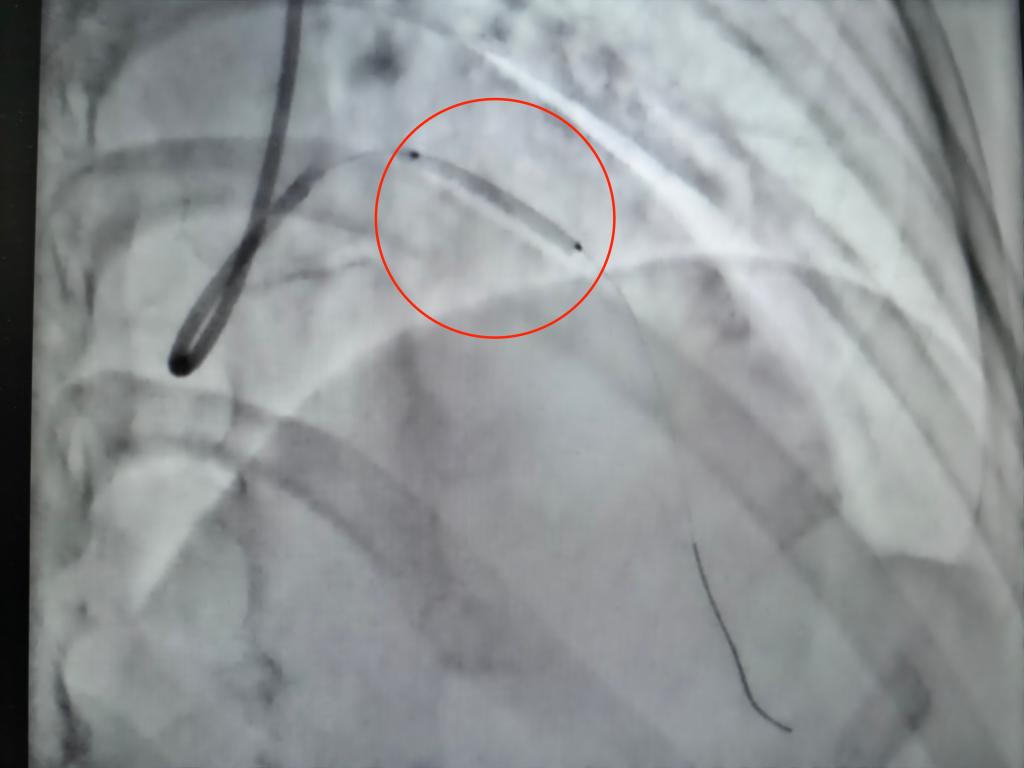

面对如此棘手的情况,河南省中医院五龙口院区组织心病科、肿瘤科、介入科等多学科专家联合会诊。经过充分的讨论和细致的评估,专家团队提出分步解决方案:第一步,采用药物球囊扩张术来解决患者的冠脉狭窄问题。与传统的心脏支架相比,药物球囊具有独特的优势:它能够在扩张狭窄血管、恢复血流的同时,无需在血管内永久植入异物,术后仅需短期的抗血小板治疗,这显著降低了后续肿瘤手术中的出血风险以及血栓风险;第二步,患者及时行肿瘤手术;第三步,观察心脏症状,复查冠脉CT或造影,若冠脉形态维持良好则继续药物治疗,若再发狭窄即可给予支架治疗。专家团队从而破解患者所面临的治疗矛盾。

2026年3月20日,在我院心脏介入团队杨凤鸣副主任、曹程浩副主任医师的精心操作下,患者的冠脉药物球囊扩张术顺利完成。术后进行的造影结果显示,原本前降支血管95%的狭窄成功解除,血流恢复通畅状态。目前,患者的生命体征平稳,为她在近期内安全地进行卵巢肿瘤手术奠定了坚实的基础。